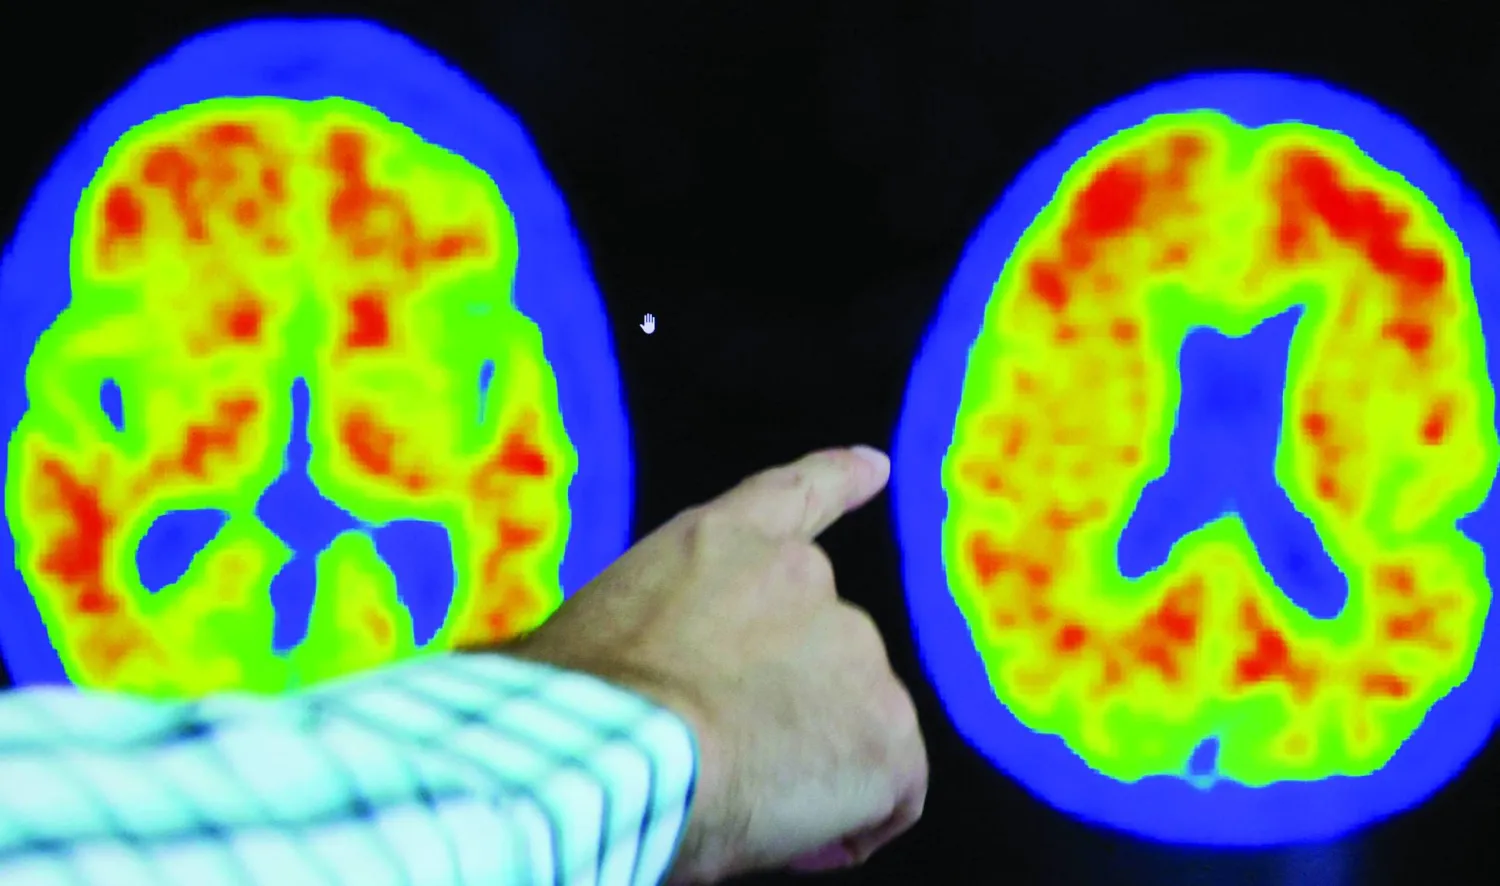

ومرض ألزهايمر هو مرض عصبي تنكسي يتميز بالتدهور التدريجي للوظائف المعرفية، مثل الذاكرة واللغة والتفكير والسلوك والقدرات على حل المشكلات. وهو السبب الأكثر شيوعاً للخرف، حيث يمثل 60 – 80 في المائة من الحالات. والغالبية العظمى من المصابين بمرض ألزهايمر هم من كبار السن، على الرغم من أنه يصيب أيضاً الأشخاص الأصغر سناً الذين تقل أعمارهم عن 65 عاماً.